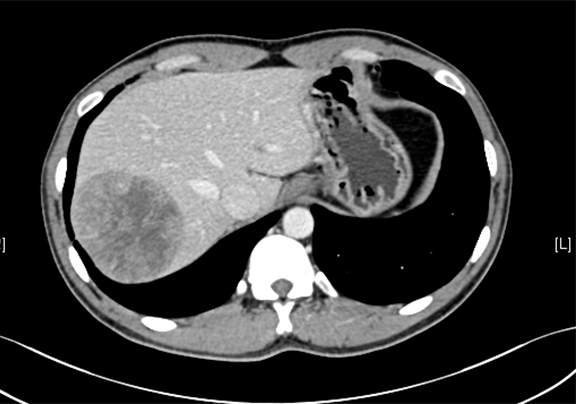

术前CT检查:

平衡期

下腹部增强CT示:肝右后叶占位性病变,考虑肝癌可能性大。